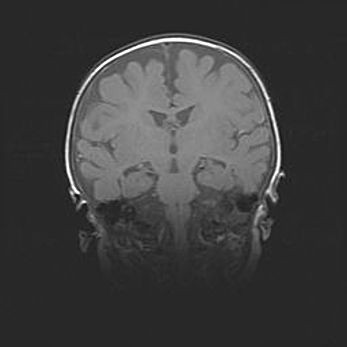

Лейкомаляция с кистозно-глиозной дегенерацией головного мозга.

Возраст: 2 месяца 25 дней

Вес: 6400 г

Окружность головы: 40 см

Срок гестации: 41 неделя

Лейкомаляцию относят к ишемически-гипоксическим повреждениям головного мозга, диагностируемым у новорожденных. При лейкомаляции в головном мозге обнаруживают очаги некроза, возникшие после тяжелой гипоксии и нарушения кровотока. В процессе морфогенеза очаги проходят три стадии: 1) развития некроза, 2) резорбции и 3) формирования глиозного рубца или кисты. Перивентрикулярная лейкомаляция (ПЛ) встречается примерно в 12% случаев среди новорожденных, обычно – у недоношенных детей, причем, частота ее зависит от массы, с которой младенец появился на свет. Наибольшее число малышей страдает лейкомаляцией, если масса при рождении 1500-2500 г.